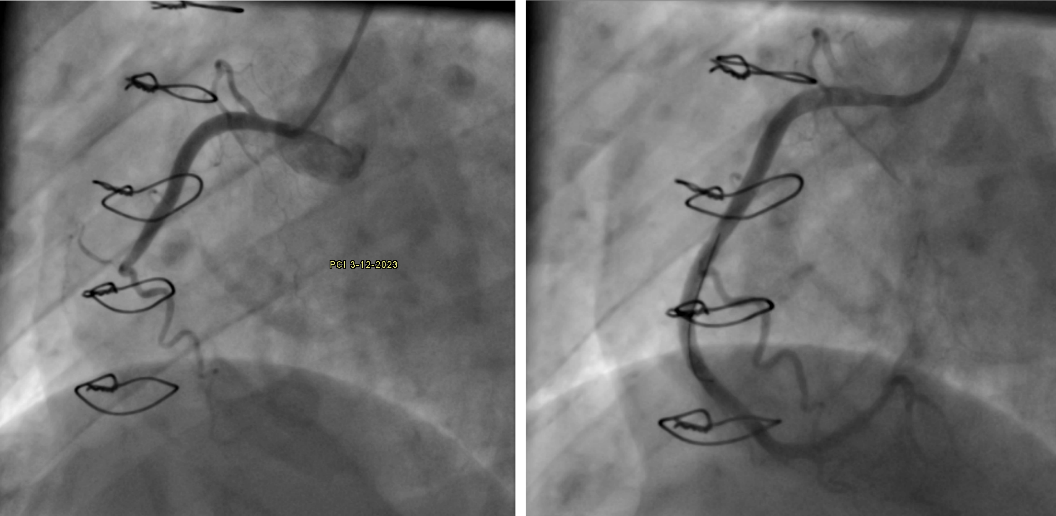

this picture shows the incresed RCA perivascular fat in a CCTA done 8 months before the acute MI compared with normal RCA perivascular fat in a CCTA done 2 years prior (both are done as a routine follow up and the patient had no symptoms at time)